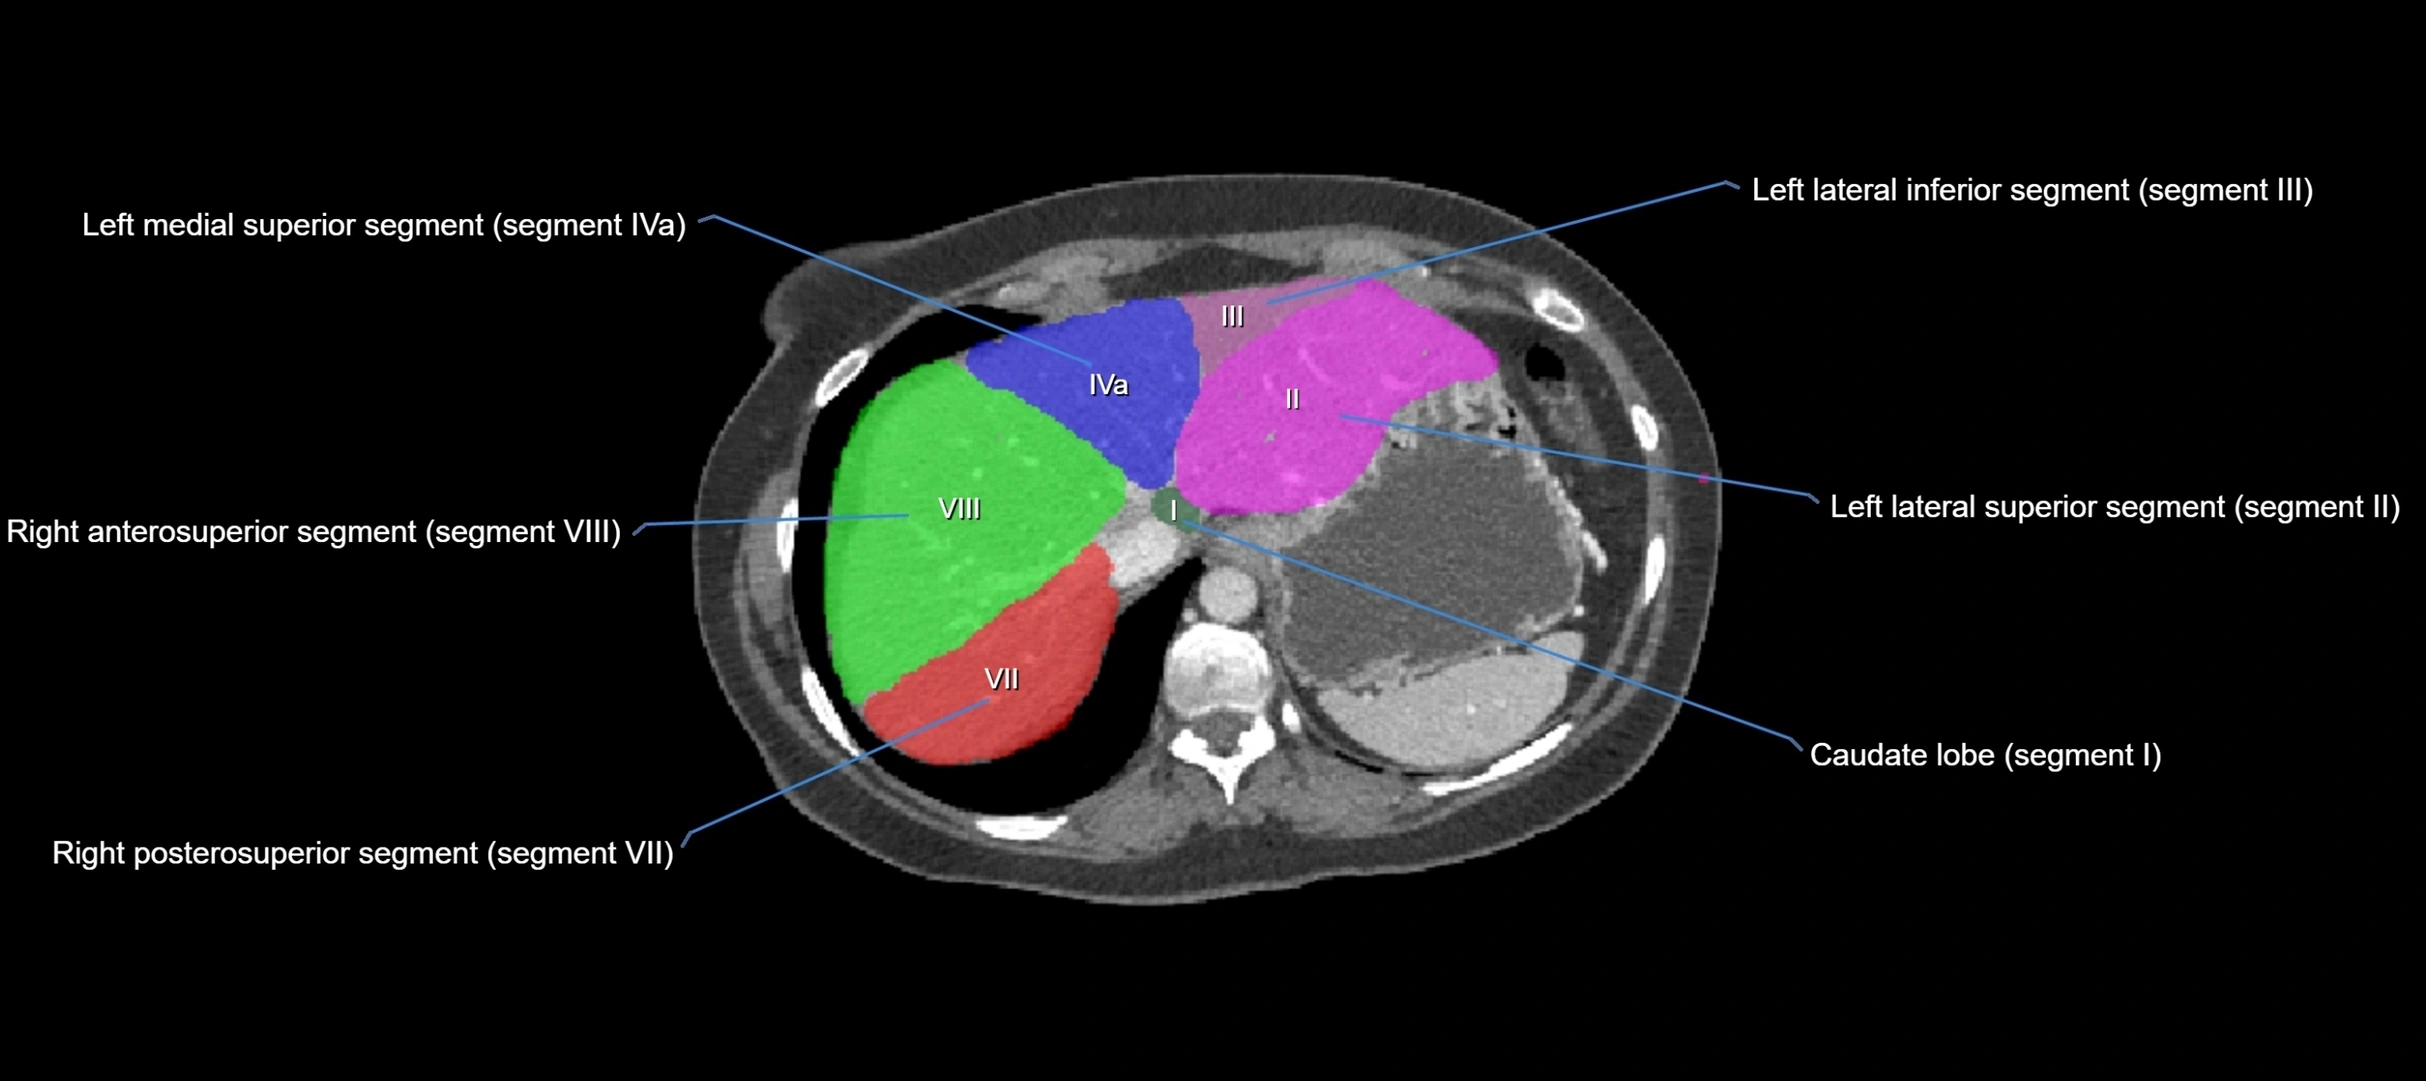

The caudate lobe of the liver is a distinct anatomical subdivision of the liver, designated as segment I in Couinaud’s classification. It lies on the posterior surface of the liver, between the fissure for the ligamentum venosum (left boundary) and the groove for the inferior vena cava (IVC) (right boundary). Superiorly, it is related to the posterior liver surface, and inferiorly it is separated from the left lobe by the porta hepatis.

The caudate lobe is unique because it receives dual portal venous and arterial inflow from both the right and left portal veins and hepatic arteries. It also has independent venous drainage directly into the IVC via multiple small hepatic veins, unlike other lobes that drain through the three main hepatic veins.

• Segment I (Couinaud classification)

CT Image

image